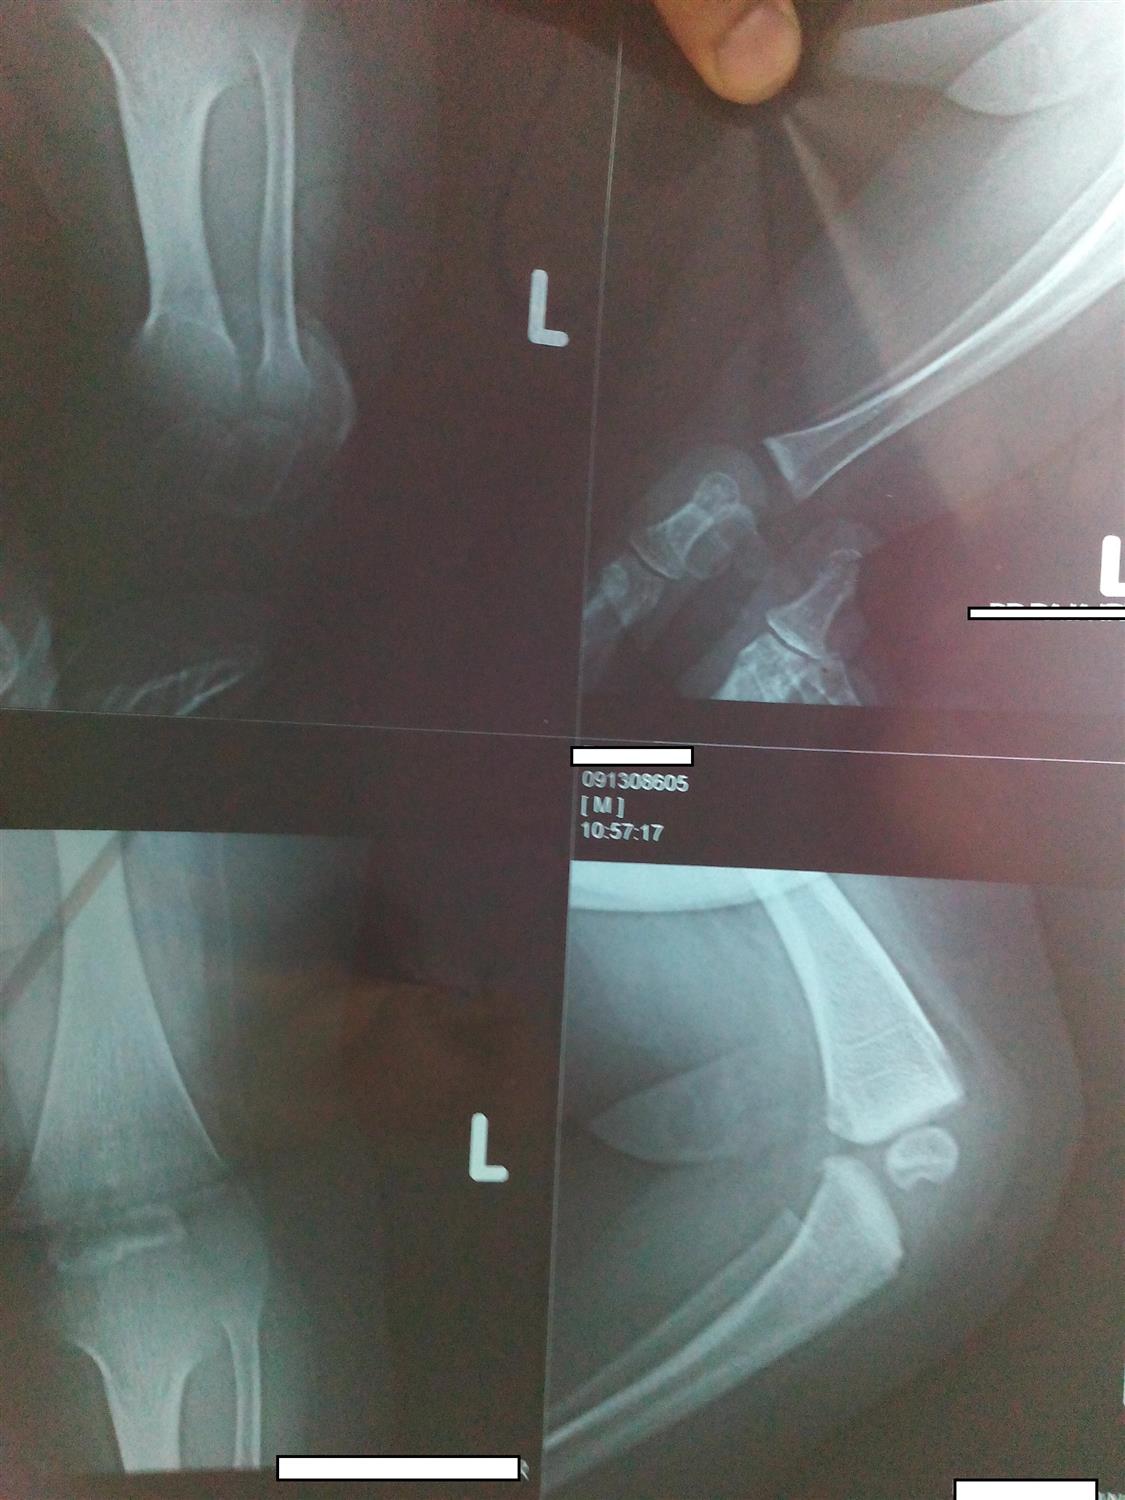

Arm Compartment Syndrome Orthobullets . Acute compartment syndrome (acs) is a surgical emergency. There have been multiple causes of upper arm compartment syndrome. Compartment syndrome is a surgical emergency. Compartment syndrome is a condition in which increased tissue pressure within a limited space compromises the. An upper arm compartment is a rare type of compartment syndrome. A table outlining the emergency evaluation and management of acs. Failure to diagnose it and delays in decompressing the involved compartment(s). Hand & forearm compartment syndrome are devastating upper extremity conditions where the osseofascial.

Hand & forearm compartment syndrome are devastating upper extremity conditions where the osseofascial. Compartment syndrome is a condition in which increased tissue pressure within a limited space compromises the. A table outlining the emergency evaluation and management of acs. There have been multiple causes of upper arm compartment syndrome. Failure to diagnose it and delays in decompressing the involved compartment(s). Compartment syndrome is a surgical emergency. An upper arm compartment is a rare type of compartment syndrome. Acute compartment syndrome (acs) is a surgical emergency.

Arm Compartment Syndrome Orthobullets Compartment syndrome is a surgical emergency. An upper arm compartment is a rare type of compartment syndrome. Compartment syndrome is a surgical emergency. Hand & forearm compartment syndrome are devastating upper extremity conditions where the osseofascial. Acute compartment syndrome (acs) is a surgical emergency. A table outlining the emergency evaluation and management of acs. Compartment syndrome is a condition in which increased tissue pressure within a limited space compromises the. There have been multiple causes of upper arm compartment syndrome. Failure to diagnose it and delays in decompressing the involved compartment(s).